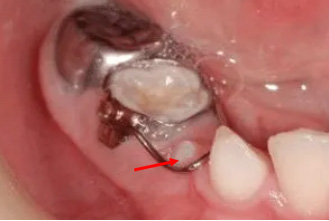

箭头所指处为恒牙已萌出